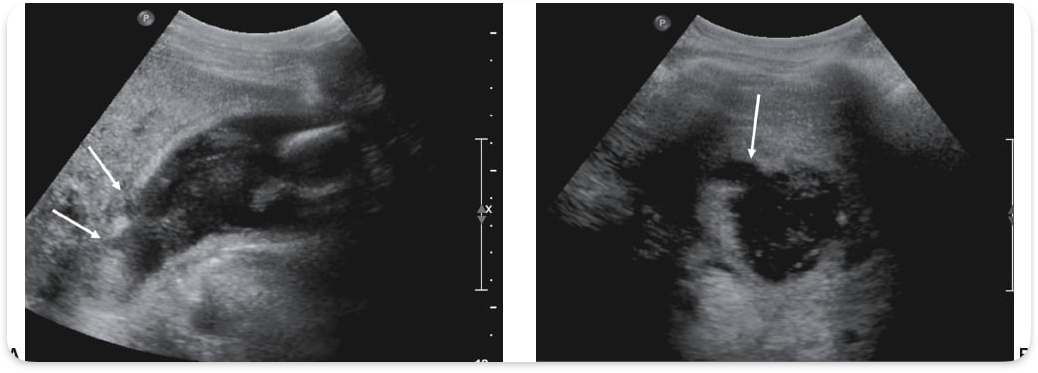

Emphysematous cholecystitis

Acute cholecystitis caused by "gas-forming“ infection

Mostly found in diabetic patients

Champagne sign

Echogenic bubbles visualized on anterior wall